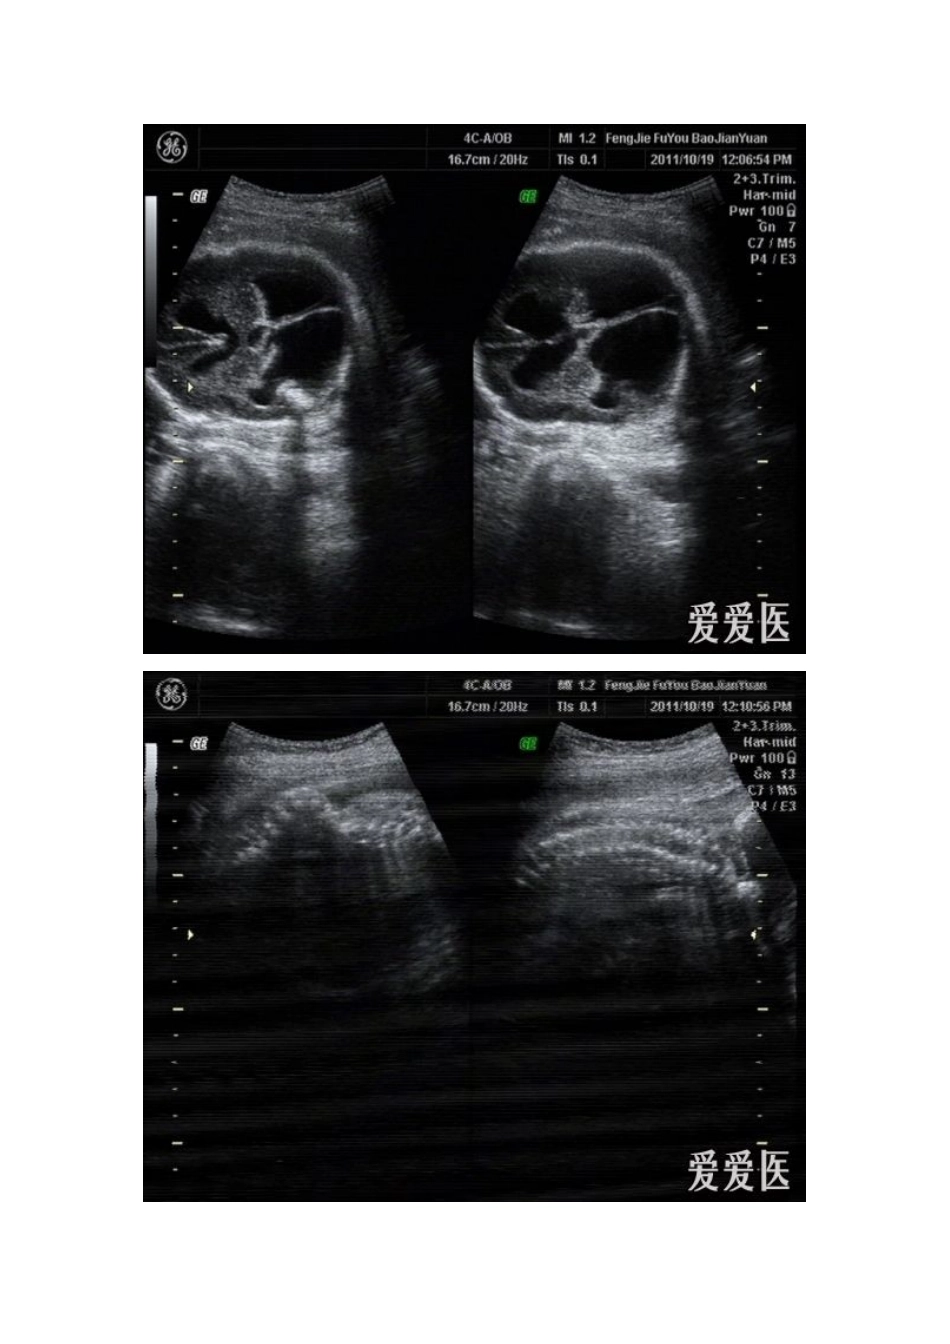

脑积水:是由于各种原因引起脑脊液在脑室腔内过多积聚,出现脑室扩张。脑积水可使胎头体积增大,颅缝增宽,骨质变薄。脑室扩张或腩积水最常见的原因是中脑导水管狭窄,其他常见原因包括:颅内感染导致脑脊液产生、吸收和回流障碍;脑结构发育异常;神经管畸形;染色体异常;多发畸形综合征。因此当发现颅内异常积液时,一定要仔细扫查其他可能的病变。超声表现:1.脑室扩张诊断标准妊娠20周后,侧脑室或小脑延髓池宽度超过10mm就应警惕腩室扩张积液,应密切随访观察其转归。若追踪观察过程扩张进行性增大,可诊断脑积水。正常胎儿在妊娠20周后,侧脑室外恻至中线距离与脑中线至颅骨板之间的距离之比(腩室率)小于l/3,若大干1/3即提示脑积水的存在。2.中脑导水管狭窄表现双侧侧脑室和第三脑室扩张,进行性加重。严重时侧脑室极度扩张,脉络膜从漂浮往脑室中,大脑组织受压变薄、脑中线漂浮,头围增大,脑室率多大于l/2,常合并羊水过多,第三脑室也相应扩张,见图5―2―22。交通性脑积水也有上述表现,偶尔可以见到蛛网膜下腔扩张、第四脑室扩张。鉴别诊断:脑积水应与脑实质内病变引起的局限性积液鉴别。由于颅内感染、颅内血管闭塞、脑组织发育不良等因素导致脑积液改变,表现为颅内出现不对称局限性液性暗区、相应的颅内结构缺失或受压变形,例如水脑、孔洞脑(脑穿通畸形)等。注意:严重的脑积水诊断并不难,但20周以前,个别的单纯侧脑室扩大,可能为暂时性的失调,需定期监测,谨慎诊断。二.胎儿脊柱在骨化过程中若不融合,或仅部分融合,则形成脊柱裂(spinabifida),常合并脊膜膨出、无脑等其他中枢神经系统畸形。绝大多数脊柱裂为背侧裂,发生在腰椎或骶椎。其发生与染色体异常、环境因素有关。大部分脊柱裂为开放性,小部分为隐性脊柱裂,后者无脊膜膨出、皮肤和皮下软组织正常,超声容易漏诊。超声表现:1.椎骨变形、缺损从胎儿脊柱的背面冠状扫查,脊柱背侧椎弓的两条平行串珠状强回声间距离局部变宽,横切而上在椎管外围由椎体和椎弓组成的闭合性三角形变成开放性,两椎弓分开,呈V形或U型。可以合并脊柱侧弯或后突畸形。2.脊膜膨出开放性脊柱裂在脊柱病变的部位,皮肤、皮下软组织也有缺损,皮肤延续性中断,局部见大小不等、边界清晰、有薄壁的囊性膨出物,常随胎动在羊水中漂动,局部可见脊椎裂声像。轻度脊膜膨出尤其是位于骶尾部时,容易漏诊。3.合并异常常合并颅内积液。由于脊膜膨出、枕骨大孔疝形成,造成颅内负压,小脑受挤压变形,反折呈“香蕉形小脑”,两侧顶骨内陷形成“柠檬头”征。另外常合并马蹄内翻足、羊水过多等。鉴别诊断:脊椎裂脊膜膨出应与骶尾部畸胎瘤鉴别。后者囊肿内为不均质混合回声、表面有皮肤覆盖、脊椎骨无异常,藉此声像可以鉴别。临床评价:脊柱裂预后差,生存率低。轻度的脊柱裂出生后可行修补,但手术后有较高的残废率和智力低下,严重者应终止妊娠。注意:脑积水胎儿常合并脊柱裂